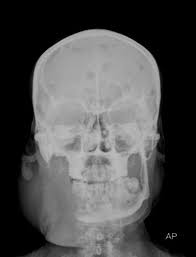

Multiple Myeloma Radiology - Headneckbrainspine : Multiple myeloma (mm) is a debilitating malignancy that is part of a spectrum of diseases ranging from monoclonal gammopathy of unknown significance (mgus) to plasma cell leukemia.

Multiple Myeloma Radiology - Headneckbrainspine : Multiple myeloma (mm) is a debilitating malignancy that is part of a spectrum of diseases ranging from monoclonal gammopathy of unknown significance (mgus) to plasma cell leukemia.. Multiple myeloma is the second most common form of. 16,000 new cases and 11,000 deaths. Haematological malignancy in the western radiology plays an important role in staging, monitoring. Learn more about the symptoms, causes, diagnosis, risk factors, and treatment of multiple myeloma. } myeloma cells produce paraproteins which are found in blood and urine (protein bence jones).

Multiple myeloma is a monoclonal gammopathy and is the most common primary malignant bone neoplasm in adults. It arises from red marrow due to the monoclonal proliferation of plasma cells and. Healthy plasma cells help you fight infections by making antibodies that recognize and attack germs. Multiple myeloma (mm), also known as plasma cell myeloma and simply myeloma, is a cancer of plasma cells, a type of white blood cell that normally produces antibodies. A report from international myeloma.